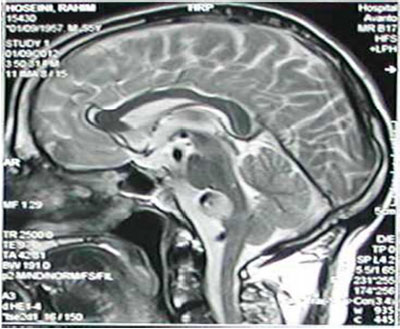

1.2  方法 患者均给予动态磁敏感对比增强灌注成 像(DSC-PWI)、MRA、3D-ASL 检 查, 均 采用德国西门子公司的 Avanto DOT 1.5 T 全身磁共振成像系统。(1)MRA 检查:采用三维时间飞跃序列;参数设置:脉冲序列重复时间 25 ms,回波时间 2.7 ms, 层厚 1.4 mm, 矩阵 320×192,视野22 cm,脉冲重复激发次数 1.0。检查完成后由 3D MIP 重建处理,生成血管图像,图像上标注患者血管情况,由 2 名高资历影像科医师分别阅片,评估脑内动脉狭窄程度,存在脑内动脉狭窄为 TIA 阳性, 反之则为阴性。(2)3D-ASL 检查: 采用梯度自旋回波序列;参数设置:脉冲序列重复时间4640 ms,回波时间 10.7 ms,层数 36,层厚 4.0 mm,矩阵 64×64,标记后延迟 2 s, 宽带 62.5 Hz, 视野 24 cm,分辨率 512。检查完成后数据上传至 GE ADW 4.6 工作站处理,生成全脑血流量伪彩图,通过观察伪彩图颜色变化判断脑内灌注情况,若伪彩图存在红色区即为灌注充足,存在黑色区即为灌注缺失,伪彩图存在蓝绿区即为灌注不足。选择灌注异常最大层面选取感兴趣区,同时以大脑中线为轴,于健侧选取同样大小的镜像区,计算两侧区域相对脑流量(rCBF)。rCBF= 感兴趣区脑流量 / 镜像区脑流量。rCBF 超过 1.1 为灌注充足,介于0.9~1.1 之间为灌注缺失,低于 0.9 为灌注不足。将灌注缺失、灌注不足定义为TIA 阳性,灌注充足定义为 TIA 阴性。(3)DSC-PWI 检查:对比剂采用钆双胺,肘前静脉注射,扫描序列选择梯度回波序列,扫描完成后根据 DSC-PWI 灌注伪彩图的颜色变化判断,若伪彩图存在红色区为灌注充足,存在黑色区为灌注缺失,存在蓝绿区为灌注不足,将灌注缺失、灌注不足定义为 TIA 阳性,灌注充足定义为TIA 阴性。

TIA 是以一过性脑或视网膜功能障碍为典型特征的脑血管疾病,患者常表现为感觉障碍、短暂性失语、瘫痪,且症状可反复发作 [6]。早期诊疗可帮助 TIA 患者控制疾病发展,其中 MRA、3D-ASL 检查均为临床近年常用的新型影像学方法 [7]。MRA 检查是基于流入增强效应、流动去相位效应、饱和效应研发的血管成像方法,具体过程为利用带有预饱和带的 3D 层块头端饱和静脉血流,动脉血液反向流动进入 3D 层块,因其未饱和而产生信号,通过读取信号得到直观血管图像 [8]。该方法采集的图像清晰,血管细微结构明显,分辨率高。3D-ASL 检查的原理是将水质子作为内源性对比剂,先利用反转脉冲对上游动脉中的水质子进行反转与标记, 待延迟后,标记水质子流入成像层面,对标记相、未标记相减影后即得血流灌注图 [9]。3D-ASL 检查具有采集快、成像快、定位准确、信息采集完全、图像质量高等优点 [10]。本研究结果显示,3D-ASL 检查诊断 TIA 的灵敏度、准确度均高于 MRA 检查诊断。这可能是因为部分脑动脉狭窄患者并不存在血流灌注减低情况,此外,MRA 检查血流缓慢或血管迂曲的患者时易出现信号丢失现象,导致假阳性数量增多 [11]。值得注意的是,3D-ASL 检查诊断TIA 亦可能出现错诊、漏诊现象,这与 3D-ASL 分辨率较低有关,若患者是因细微栓子阻塞小血管引发 TIA,或血管狭窄发生于颅外段引发的低灌注, 3D-ASL 均无法有效显示,因此临床在实际诊疗过程中,需谨慎判断患者病变情况,选用适当的方法进行诊断。